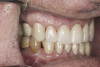

(9.) Preoperative right lateral, closed view.

Figure 9

(10.) Preoperative anterior, closed view. Note the end-to-end occlusion of the anterior teeth and the wear on the incisors and centrals resulting in no anterior or canine guidance.

Figure 10

(11.) Preoperative left lateral, closed view.

Figure 11